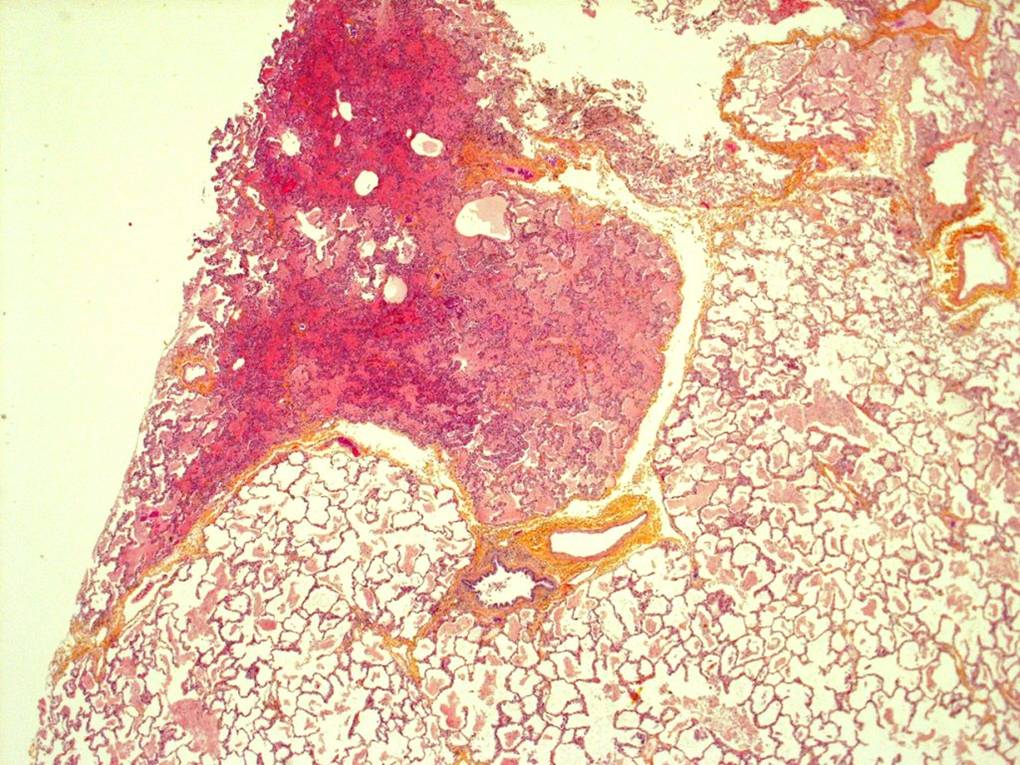

A lung biopsy was performed 24 hours after the steroids were commenced. The biopsy of the right middle lobe and right lower lobe was performed via a right thoracostomy. It was tolerated well with no air leak and no chest tube was required.

Please interpret the histology slides: (The final slide is a Periodic acid Schiff stain (PAS))

| figure 3 | figure 4 | figure 5 |